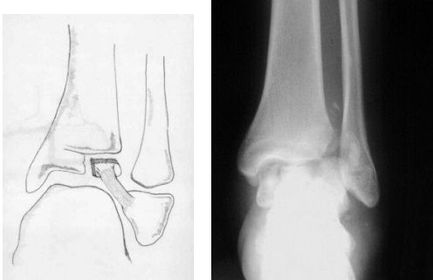

| What type of fracture is this? How does it occur? | Tillaux fracture - a fracture of the anterolateral tibial epiphysis that is commonly seen in adolescents. The fragment is avulsed due to the strong ATF ligament in an external rotation injury of the foot. |

| What classification system is this? Describe the 3 classifications | Weber Ankle Fracture Classification A = Fracture below syndesmosis B = Fracture begins at joint level & extends proximally in an oblique fashion C = Fracture above the joint line |